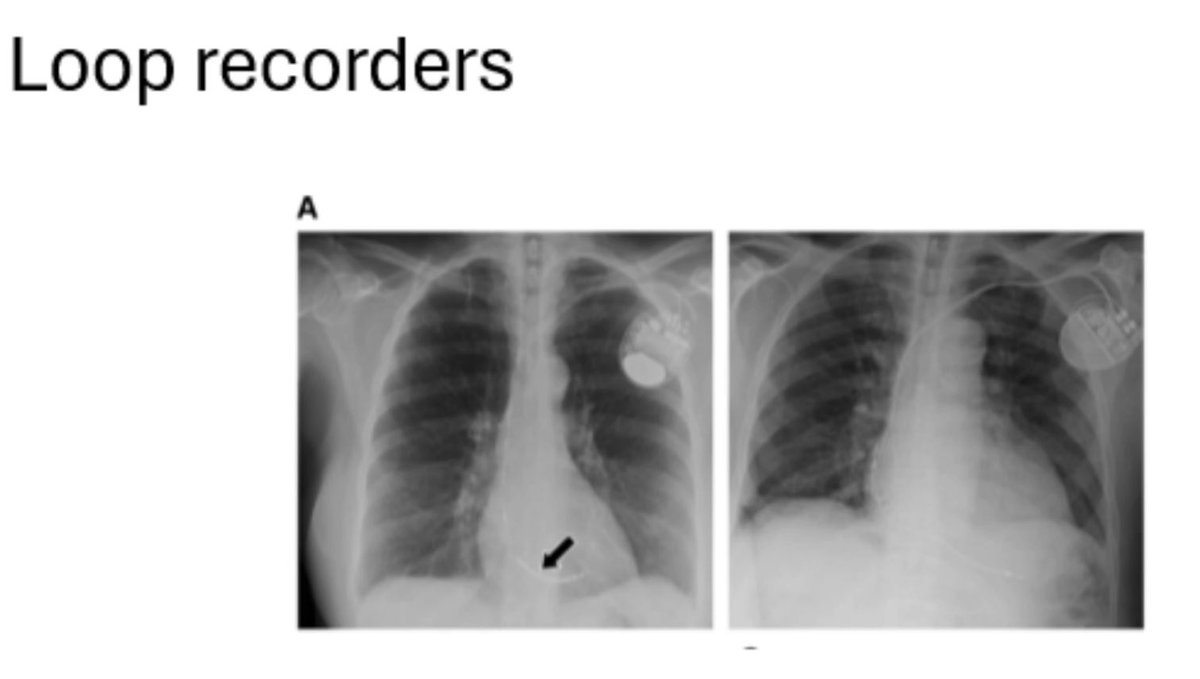

Very honored to participate in such an important AHA initiative on awareness, early detection and treatment of cardiac implantable electronic device (CIED) infections. This is just the beginning… Alexandra Wick, MD UW–Madison UW-Madison Division of Cardiovascular Medicine University of Wisconsin Department of Medicine AHAMeetings American College of Cardiology Heart Rhythm Society

#Treat2BeatCIEDInfection Patient advocacy, coordination across med-surg specialties, institutional support, leverage of established EHR capabilities, innovative thinking, patient-centered care and much more. A recipe for improving outcomes Elaine Wan Bruce Wilkoff AHA Research

And the first AHA National CIED Infection Initiative document is here for all of us to read, learn, distribute, educate and join the cause! heart.org/-/media/Files/… Bruce Wilkoff Elaine Wan Emory University #treat2beatCIEDinfection

1/ This provides a framework for the periprocedural management of patients with CIEDs, encompassing the planning phase, procedure, & subsequent care coordinated with the primary device managing clinic. ✍🏽 A.J. Rogers Elaine Wan Michael Lavelle Miguel A Leal Sarah A. Stone, MD

1/ Understanding & managing patients with CIEDs is important as interference with device function may result in hemodynamic disturbances or arrhythmias. 📷 The cycle of periprocedural management of CIEDs ✍🏽 A.J. Rogers Elaine Wan Michael Lavelle Miguel A Leal Sarah A. Stone, MD